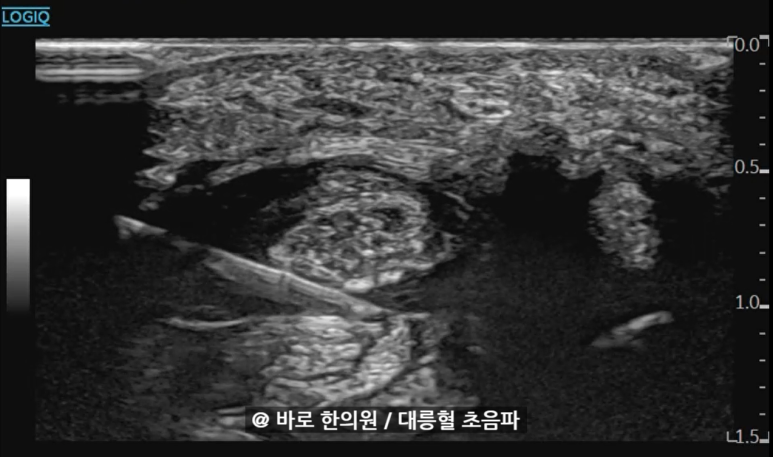

특히 대릉혈 초음파에서

선천적으로 정중신경이 2개로 나뉜

**이분 정중신경(bifid median nerve)이신 분들은

손목터널증후군이 훨씬 잘 생기죠.

대릉혈(PC7)에서

표준 경혈 초음파 영상과 달리

정중신경이 얼마나 부어있는지,

SSCT가 얼마나 섬유화되어

주변 힘줄과 유착이 생겼는지를

눈으로 직접 확인합니다.

영상을 보시면 훨씬 이해가 쉬우실 텐데요.

초음파로 이렇게 문제가 되는 부위를 정확히 찾아내